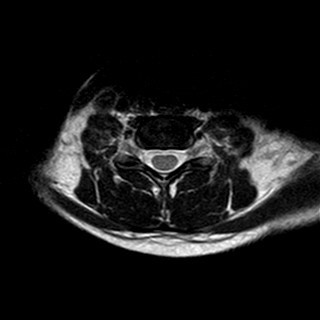

A 26 years old woman with

MRI Investigation done on 22Aug2015